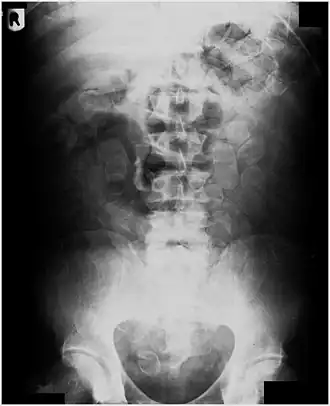

Plain radiograph of the abdomen of a drug "mule" showing swallowed drug capsules

Abdominal X-ray showing swallowed packages of cocaine.

Routine detection of the smuggled packets is extremely difficult, and many cases come to light because a packet has ruptured or because of intestinal obstruction. Unruptured packets may sometimes be detected by rectal or vaginal examination, but the only reliable way is by X-ray of the abdomen. Hashish appears denser than stool, cocaine is approximately the same density as stool, while heroin looks like air.[11][12]